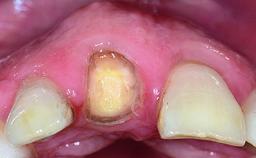

A healthy 23-year-old female patient was referred for a consultation on replacing tooth 21 with an implant-supported restoration. The patient had recently moved to the area and reported a history of endodontic and periodontal treatment for tooth 21. The tooth had been deemed non-restorable by her previous periodontist but since she was going to be moving, he recommended consulting to a dentist in her new city to continue her treatment. A review of her medical history yielded no significant findings and no known drug allergies. The analysis of her smile revealed a medium to high symmetrical smile line and a slightly discolored tooth 21.

Lip Line No exposure of papillae Exposure of papillae Full exposure of mucosa margin

Periodontal Phenotype Low-scalloped, thick Medium-scalloped, medium-thick High-scalloped, thin

Shape of Tooth Crowns Rectangular Triangular

Soft Tissue Anatomy Intact Defective